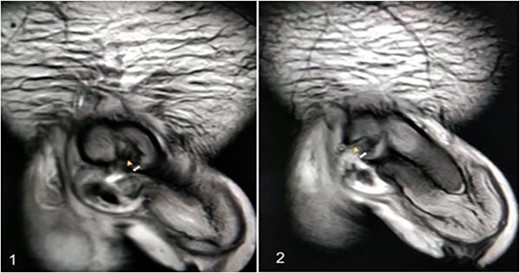

A 37-year-old male presented with a history of a ‘snap’ sound and immediate detumescence of penis during intercourse, when he fell and hit the pubic bone of his partner. There was generalized swelling and pain in the penis. There was acute retention of urine, an attempt to pass a catheter failed and the patient underwent supra-pubic catheterization. On examination, there was classical ‘eggplant deformity’ of the penis with blood at the tip of the meatus. MRI showed a tunical tear on both sides at the penoscrotal junction with indistinct urethra and extensive hematoma in the proximal penile shaft (Fig. 1). With the diagnosis of a fractured penis and possible urethral injury, after proper counselling, the patient was taken up for surgery. On the table, a retrograde urethrogram (RGU) was done showing evidence of partial urethral disruption. On exploration with penoscrotal vertical incision, there was total transection of proximal penile urethra, and a 1.5 cm tunical injury of corpus cavernosum on both sides ventrally (Fig. 2). There was extensive hematoma. Corpora sutured with 4.0 prolene after reconstructing the midline septum. Urethral ends mobilized and anastomosed with 3.0 vicryl in a single layer with minimal spatulation (Fig. 3). The patient was discharged on the 5th post-operative day; Foley catheter was removed on day 21. Follow-up RGU done after 3 months showed no evidence of stricture (Fig. 4).

Reconstruction of midline septum with mobilized and anastomosed penile urethral ends.